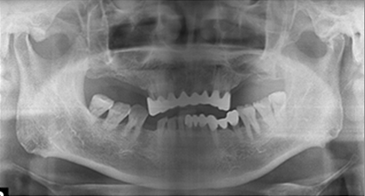

治療です。 前後写真

入れ歯の不快感を解消し、全顎インプラントを完成させます。

自然な機能と審美性の両方を満たす結果です。